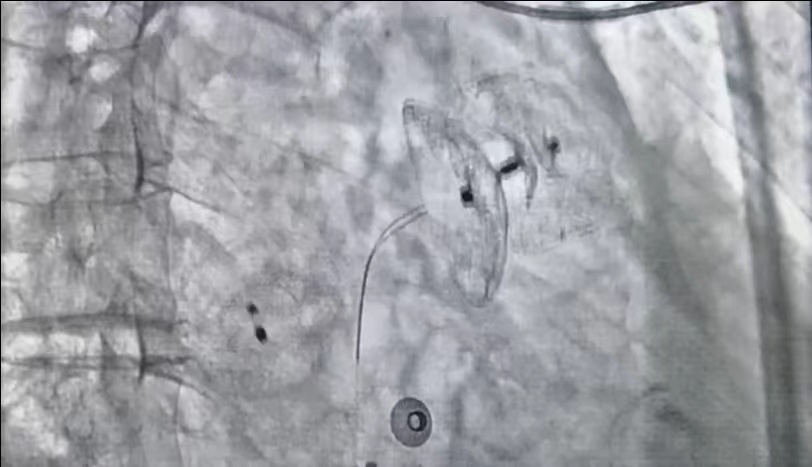

该手术难度在于不造成过大的医源性房缺的情况下完成房间隔穿刺术,在房间隔后下缘窄间隙进行精准穿刺,为后续左心耳封堵术和房颤射频消融术做好准备。同时患者心耳呈特殊的“羊角”型,上缘壁光滑,选择较大的封堵伞完成封堵,达到预期的封堵效果。

左心耳封堵术

环肺静脉射频消融术